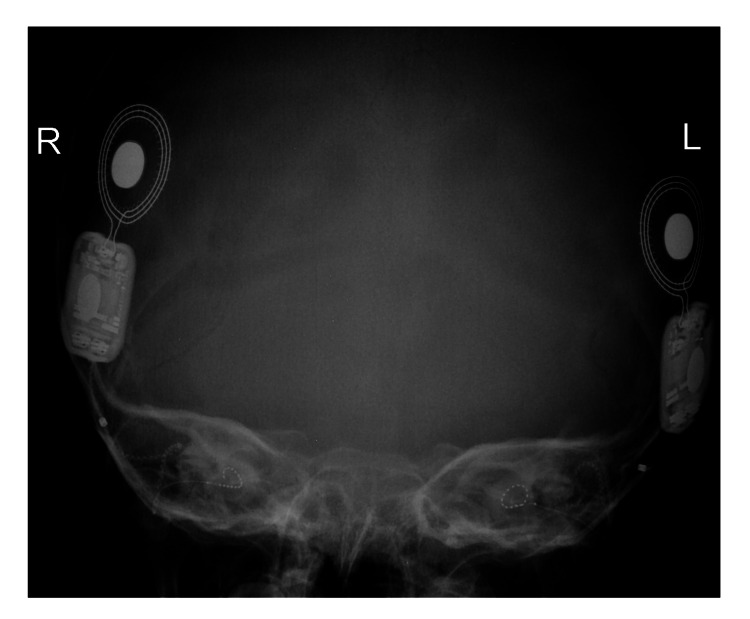

患者被 CI 委员会确定为双侧植入的候选者。 在三岁零五个月大时,进行了双侧同时人工耳蜗植入(HiRes™ Ultra #D 人工耳蜗,右 HiFocus™ SlimJ 电极和左 HiFocus™ Mid-Scala 电极,Advanced Bionics AG,加利福尼亚州,美国)。 术后 X 线显示 CI 阵列有效插入耳蜗内(图 2)。 手术后第二天开机,并给予两个 Naida CI Q70 声音处理器(Advanced Bionics AG,加利福尼亚州,美国)。

病例 2 的术后 X 线颞骨显示双耳人工耳蜗电极阵列有效插入